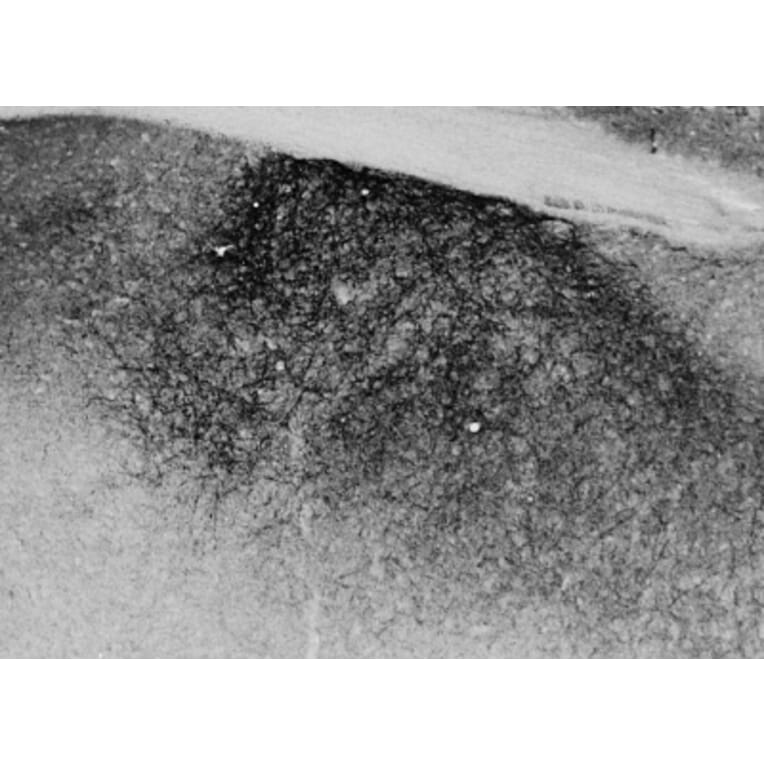

Goat polyclonal antibody to Proenkephalin for ELISA and IHC.

ELISA, IHC

ELISA: 1:32,000, WB: 0.2µg/ml, IHC: 0.02-0.05µg/ml

Mouse, Rat

Synthetic peptide corresponding to the internal region of mouse Proenkephalin.